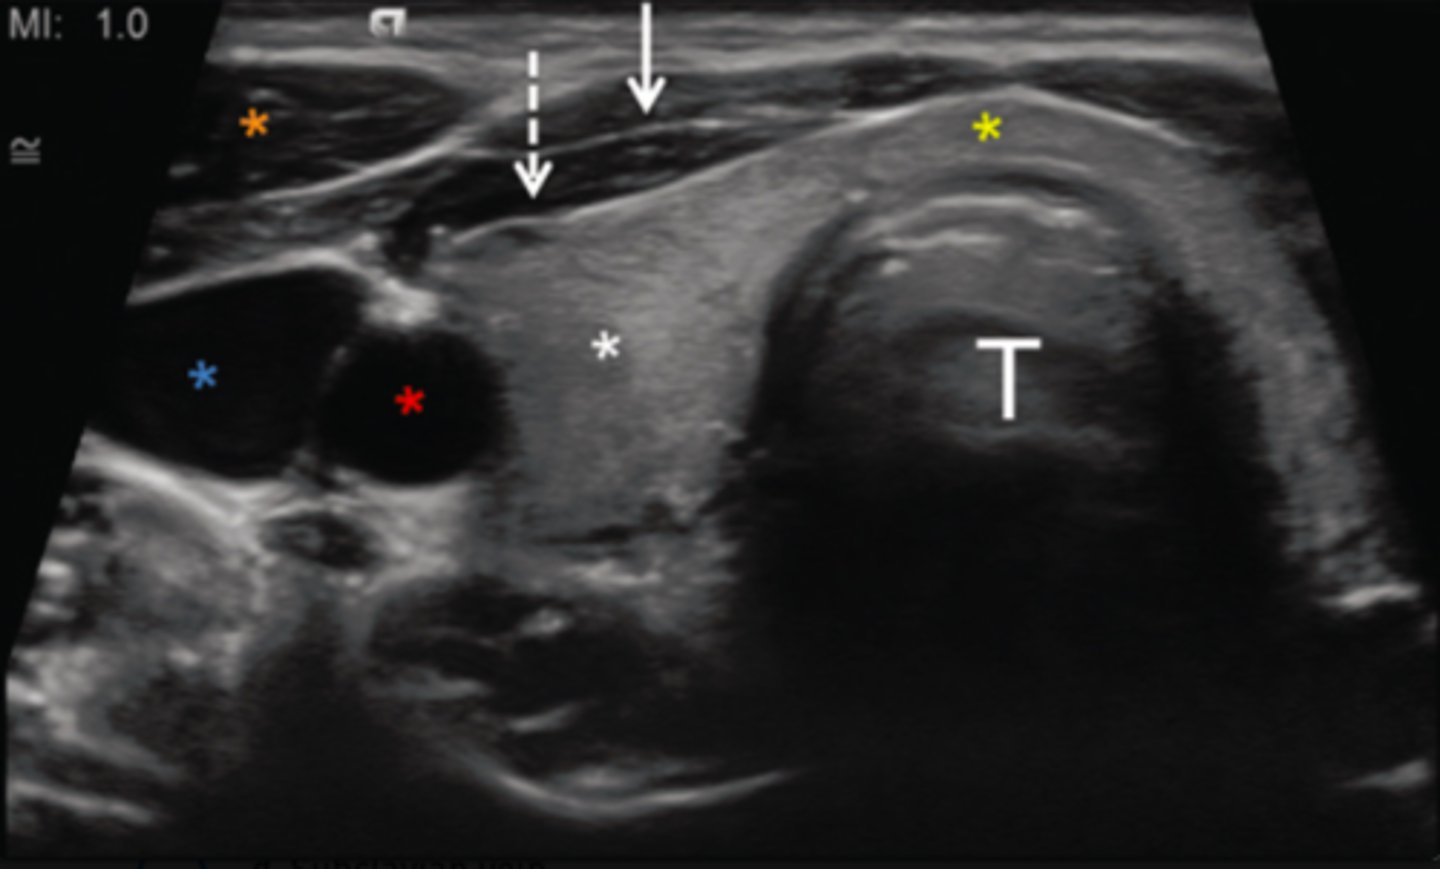

8. What does the red asterisk in Figure 12-25 indicate?

a. Common carotid artery

b. Internal carotid artery

c. Internal jugular vein

d. Subclavian vein

9. What does the blue asterisk in Figure 12-25 indicate?

a. External carotid artery

b. Internal carotid vein

c. Common carotid artery

d. Internal jugular vein

10. What does the orange asterisk in Figure 12-25 indicate?

a. Right longus colli muscle

b. Right sternocleidomastoid muscle

c. Left longus colli muscle

d. Left sternocleidomastoid muscle